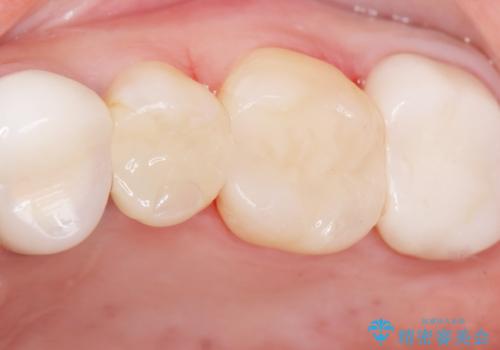

自然な仕上がりと咬み心地にご満足頂けました。

セラミックインレーは審美的で強度が高いだけではなく、適合が良いため二次う蝕にもなりにくいです。

インレーの種類:セラミックインレー e-max press